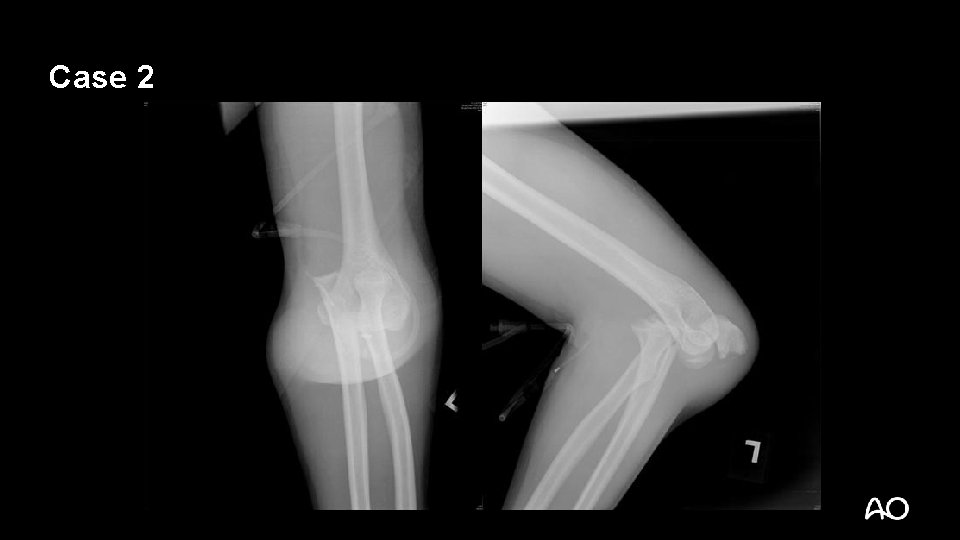

Case 2

Transolecranon fracture dislocation • Not a simple olecranon fracture • Do not treat with tension band wiring • Olecranon fracture with ANTERIOR dislocation but intact proximal radioulnar joint • Ligaments may be intact